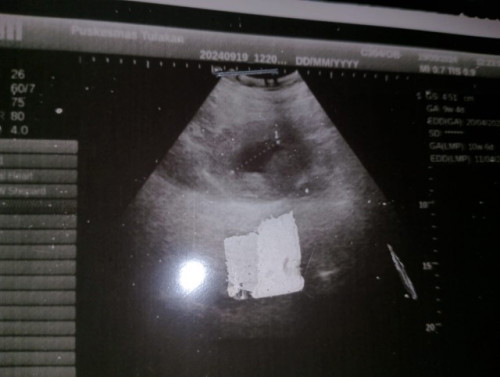

usia kehamilan 9 minggu 4 hari tapi janin belum kelihatan di USG...kira2 berbahaya apa tidak ya Bu??

sama seperti saya bund, 9w baru kantongnya saja usg di puskesmas, tapi saya nunggu 12w mau usg di dokter obgyn semoga hasilnya baik sudah ada janin dan djjnya aamiin🤲

kalo udh 9 minggu harus nya udh ada janin sama djj nya bun coba USG trans vaginal biasa y lebih jelas

harusnya udh ada Bun kmren aku Bru USG 8 Minggu udh keliatan janinnya sama djj jg dh ada. waktu 6 Minggu belum keliatan Bru keliatan kantong